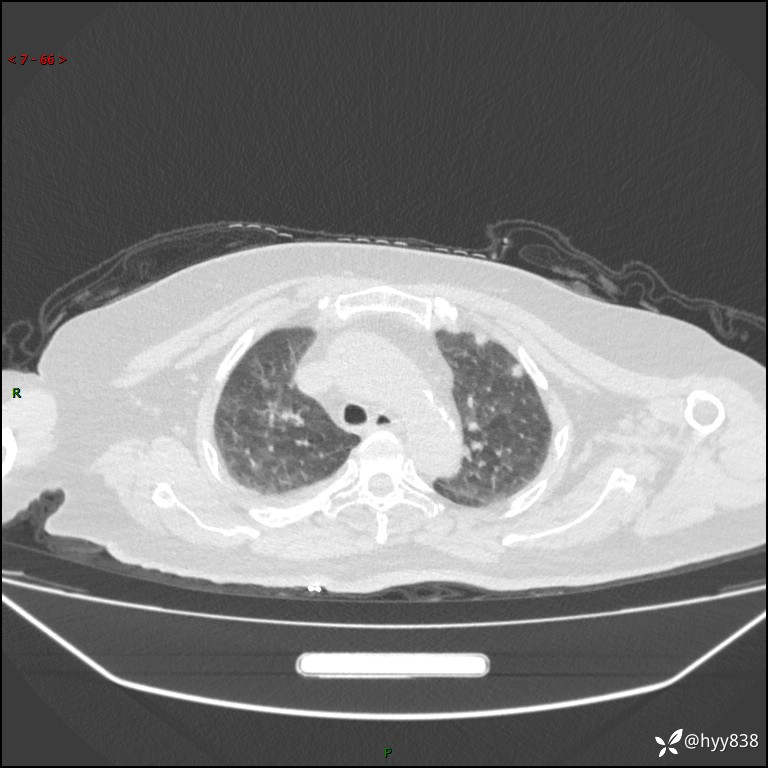

患者性别:女

患者年龄:57岁

简要病史:昏迷入院

临床诊断:昏迷

胸部 CT平扫、